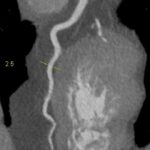

Figururile 1-9: reconstrucție în axul lung al vasului pentru arterele coronare cu evidențierea unui calibru global crescut la nivelul acestora și cu încărcătură ușoară-moderată de placă în principal calcificată

Discuţie caz nr 132: Examinările coroCT se efectuează în principal pentru aprecierea încărcăturii de placă precum și pentru evidențierea reducerilor de lumen ce necesită tratament. Această examinare a evidențiat creștere globală a calibrului arterelor coronare și o încărcătură ușoară-moderată cu placă în principal calcificată, fără a se evidenția arii de stenoză.